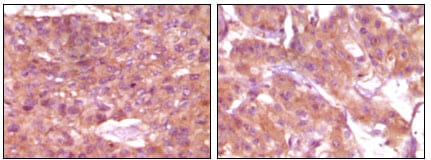

分类: 科研抗体货号: 20094别名: Desmin应用: WB,IHC,FCM反应种属: Human,Mouse,Rat,Rabbit,Monkey